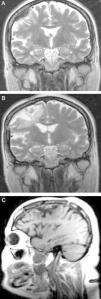

La paquimeningitis hipertrófica crónica (PHC) es un proceso inflamatorio de etiología desconocida que se caracteriza por afectar a la duramadre, provocando un crecimiento pseudotumoral de la misma. La clínica de presentación es consecuencia del efecto compresivo sobre estructuras neurológicas aunque en ocasiones se manifiesta por síntomas irritativos. El diagnóstico se realiza por exclusión de causas infecciosas, neoplásicas y autoinmunes fundamentalmente. El tratamiento esteroideo se considera la terapia más utilizada hoy en día. Se presentan 2 casos clínicos de PHC en los que se practicó resección quirúrgica de la lesión sin precisar posteriormente tratamiento coadyuvante dada la favorable evolución clínica y radiológica.

Chronic hypertrophic pachymeningitis is an inflammatory process of unknown aetiology characterised by a thickening of the dura mater causing pseudotumoural growth. Clinical manifestations are usually secondary to compression of adjacent neurological structures but may be also secondary to inflammatory processes. Diagnosis is mainly obtained by excluding infectious, neoplastic and autoimmune causes. Nowadays, steroid treatment is the most commonly used therapy. Two clinical cases of hypertrophic pachymeningitis are presented which were treated by surgery without any additional treatment and with good clinical and radiological development.